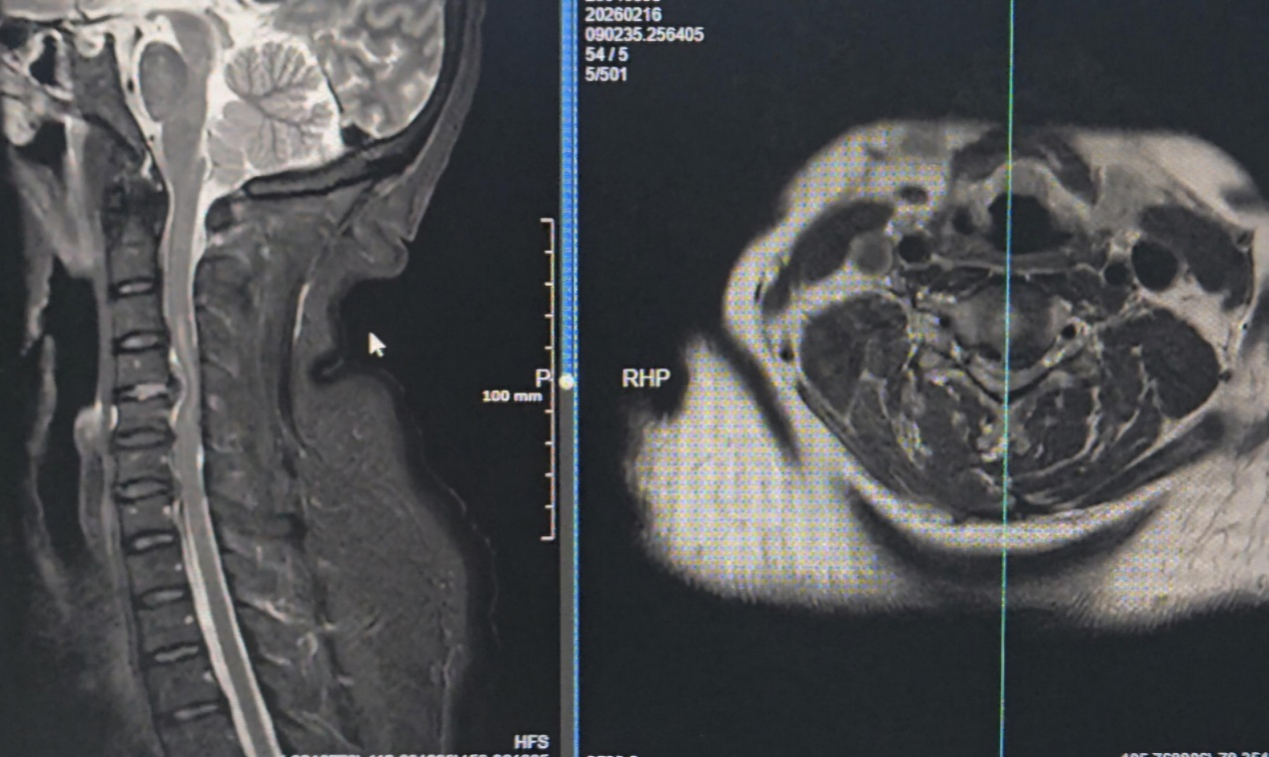

除夕当天,一名57岁女性患者因颈部疼痛加重伴四肢不全瘫踏上辗转求医路。患者三日前症状突发,当地医院检查考虑颈椎间盘急性脱出伴脊髓损伤,受限于救治能力建议转院,转诊途中患者还出现呼吸困难症状,病情危在旦夕。

家属带着患者紧急来到重庆市急救医疗中心骨科就诊,医生快速确诊后,判定其有急诊手术解除颈脊髓压迫的明确指征,医院当即开放绿色救治通道,各科室无缝衔接、高效配合,把“迅速、尽心”的院训落到实处,从患者入院到手术结束,仅用8个小时便成功解除颈脊髓压迫,阻止病情进一步恶化,为患者神经功能恢复赢得宝贵时机。